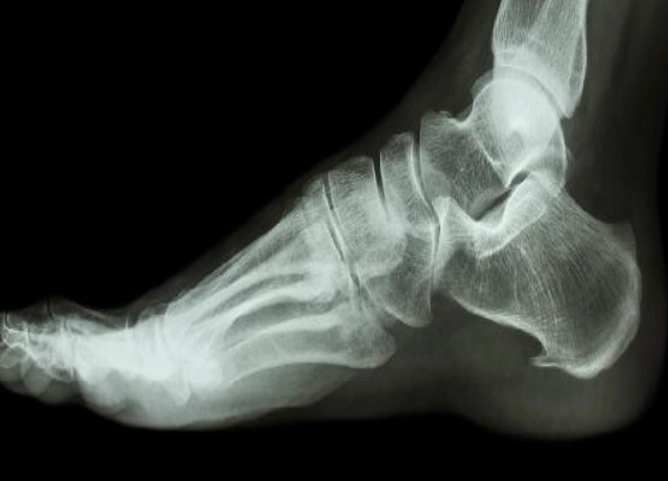

很多人聽到骨刺就嚇壞了,以為是骨頭長出尖刺會刺傷組織。其實,骨刺是骨頭邊緣多長出來的骨質增生,通常是關節長期磨損或壓力過大的結果。身體為了自我保護,才長出這些多餘的骨頭來穩定關節。

常見的骨刺位置包括腳跟、膝蓋、脊椎和手指。症狀不一定是疼痛,有些人根本沒感覺,直到壓到神經或軟組織才開始痛。我遇過一個案例,一位50歲的教師腳跟痛了半年,一直以為是足底筋膜炎,照了X光才發現是骨刺作祟。